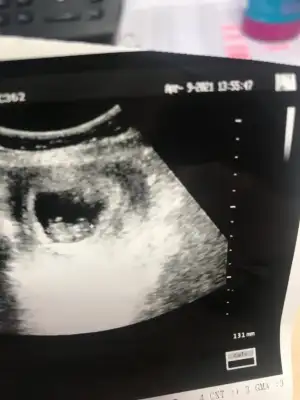

Daha küçük canım şimdilik erkek yönünde ama en iyi 11 12 13 haftalar olmalı9+1 karından usg bir tahmininiz olurmu bizim içinde![]()